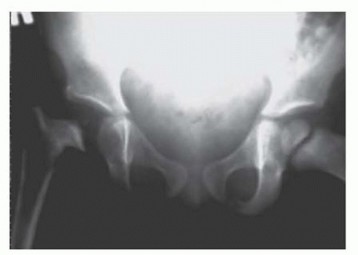

Severe sequelae with a destroyed femoral head are most commonly seen in newborns and infants and are often related to a delay in diagnosis and treatment (

FIG 5

).

FIG 5 • This 3-year-old child had septic hip arthritis missed as an infant with a week-long delay in treatment, resulting in osteonecrosis of the right femoral head.